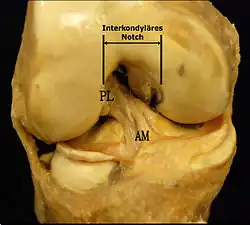

- deux ligaments croisés :

- le ligament croisé antérieur (LCA) — ligament croisé antéro-externe (LCAE), dans l'ancienne nomenclature —, son origine se trouve sur la surface pré-spinale de l'espace intercondylaire du plateau tibial, entre les cornes méniscales. Il se dirige en haut, en arrière et en dehors pour venir s'insérer sur la surface intercondylienne du condyle fémoral latéral. Le LCA croise en dehors le :

- ligament croisé postérieur (LCP) — ou ligament croisé postéro-interne (LCPI) de l'ancienne nomenclature —, de son origine, sur la surface rétrospinale de l'aire intercondylaire, il se dirige en haut, un peu en avant et en dedans, pour s'insérer sur la surface intercondylienne du condyle fémoral médial.

Les facteurs anatomiques sont soupçonnés déjà depuis longtemps. La résistance à la rupture d'un LC dépend directement de sa largeur, qui varie d'un individu à l'autre. Dans une étude anthropométrique, les LCA du genou controlatéral intact de patients victimes d'une rupture de LCA ont été comparés avec ceux d'individus de même poids corporel. Les volumes des LC ont été déterminés par IRM. Dans le groupe des blessés, le volume des LCA contralatéraux était en moyenne 1 921 mm3, tandis que dans le groupe de contrôle, il était de 2 151 mm3. Les auteurs de l'étude en concluent que les différences anthropométriques des volumes – et de la largeur qu'on en déduit – des LC ont une influence directe sur la probabilité d'une rupture de LC sans agression externe[49]. Déjà dans des études précédentes, on a établi une corrélation entre cavité ligamentaire du fémur (notch intercondylaire : voir figure) étroite, liée à des ligaments plus étroits, et un risque plus élevé de rupture de LC[50],[51],[52],[53],[54],[55]. Cependant on n'est pas arrivé à un consensus scientifique, parce que d'autres études aboutissent à des résultats opposés[43],[56],[57]. Par rapport aux hommes, les femmes ont une cavité ligamentaire plus étroite, ce qui pourrait expliquer une incidence plus élevée des ruptures de LC chez les femmes[58],[59].